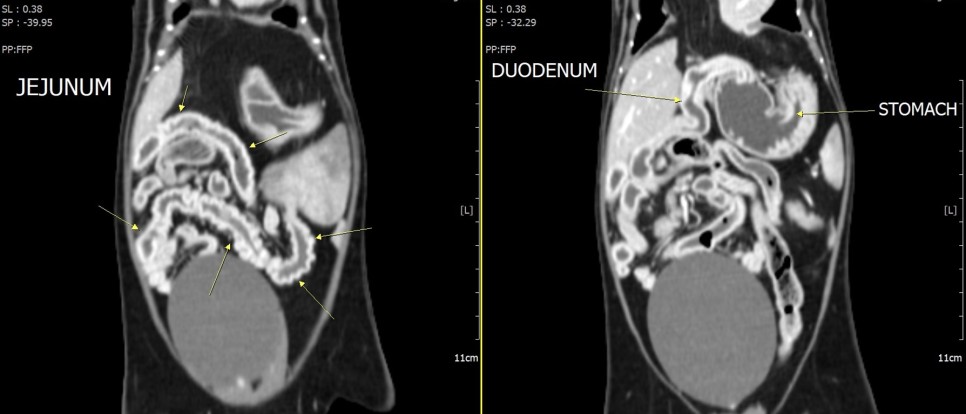

CT 검사로 횡격막 결손부의 크기와 심낭 내에 변위된 복강 장기의 위치를 정확하게 조사했습니다.

또한 선형 이물질에 의해 구불구불한 장분절이 광범위하게 확인되었습니다.